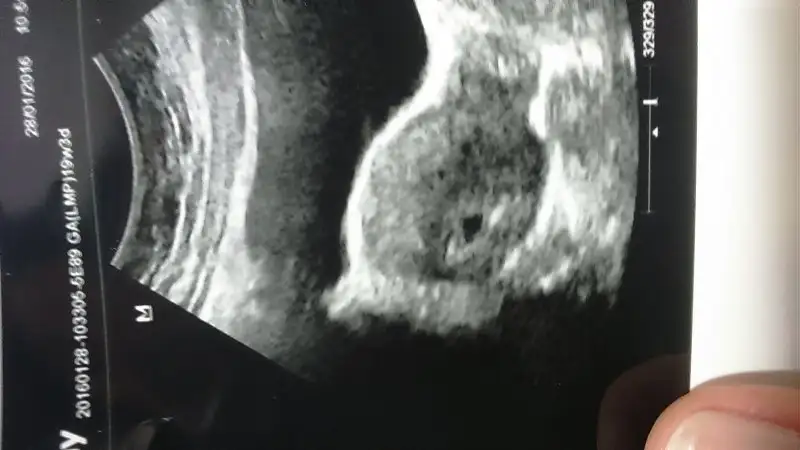

Hemen atayımAmin canim rabbim kimsenin kucağını boş bırakmasın insallah kese fotoğrafın varsa at sana canim

Ayyyy pitircik ya kuzum bu kese tahminimce 10 mm falan sanırım :)Azıcık ters yüklendi niye anlamadım ama attım :)

Bilmiyorum ki canım boyutla ilgili bişey söylemedi bizim doktorun eleştirilecek tek tarafı şu kalp atışını duyana kadar pek detaylı bilgi vermiyor kese var mı var tamam iki hafta sonra görüşelim dedi direk hatta benim risk var malum dikkat etmem gerekenleri saydı sonra da kalp atışını duyalım diğer önlemleri konuşuruz dediAyyyy pitircik ya kuzum bu kese tahminimce 10 mm falan sanırım :)